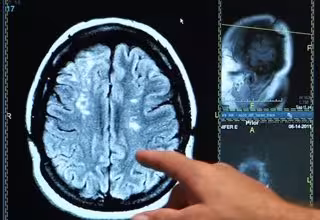

Generación X vs 'baby boomers', ¿qué generación tiene más riesgo de ictus?

Ictus, derrame cerebral, cerebro

Los nacidos entre 1945 y 1954 pueden ser considerados la "generación más sana en cuanto a accidentes cerebrovasculares", según un estudio realizado por la Universidad de Rutgers, en Nueya Jersey, Estados Unidos, que encontró la incidencia más baja de ictus isquémico en este grupo de edad en los últimos 20 años. Por el contrario, la tasa de accidente cerebrovascular es más del doble en la generación X, es decir, las personas nacidas entre 1965 y 1974, durante el mismo periodo de tiempo.